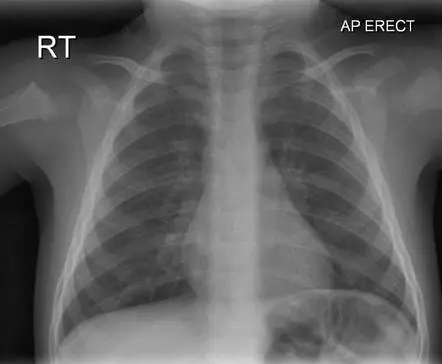

가장 기본적으로 찍게 되는 방사선 사진입니다. 사진기로 가시광선을 기록하듯, 특별한 파장을 갖는 엑스레이(광선)를 엑스레이 필름에 기록하는 원리입니다. 가시광선과 달리 엑스레이는 인체를 어느 정도 투과할 수 있는데, 공기 > 지방 > 수분 > 뼈 순서로 잘 투과합니다. 뼈는 거의 투과하지 못하기 때문에 희게 나타나고, 공기는 검게 나타납니다.

위는 흉부 엑스레이 사진인데요, 희게 나타난 뼈와, 공기가 가득 찬 폐를 관찰할 수 있습니다.

왼쪽 상단의 대문자 RT(혹은 R)는 그쪽이 오른쪽이란 뜻입니다. LT이 있으면 왼쪽이겠죠? 오른쪽 상단에 AP라고 쓰여 있습니다. 이는 anterior to posterio의 약자로, 앞에서 뒤로 찍었단 뜻입니다. 엑스레이를 환자 앞에서 쪼이고, 필름은 환자의 뒤쪽에 놓은 상태에서 사진을 찍었습니다. AP뒤에 ERECT는 사진을 서서 찍었다는 의미예요.